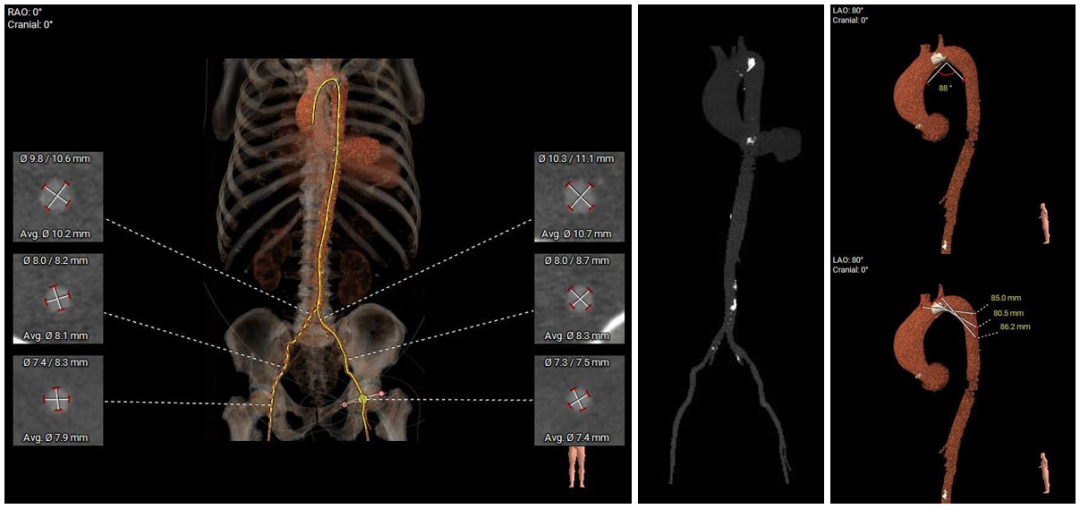

主动脉弓、腹主动脉可见钙化斑块,双侧股髂动脉未见明显扭曲、斑块,入路血管内径尚可。

外周血管入路评估

本例患者为主动脉瓣重度狭窄伴轻度反流,患者因反复严重心衰,一般状况很差,合并心肌致密化不全、脑梗死后遗症等基础疾病,无法耐受外科开胸手术,术前评估适宜行TAVR手术,有TAVR手术指征。术前CT分析提示患者为Type0型二叶瓣,瓣环径较大,达到28.8mm,瓣叶轻度增厚伴钙化,瓣上限制较重,给瓣膜的锚定增加了一定的难度,瓣膜植入后存在形变、移位和瓣周漏的风险。患者为严重横位心,升主动脉瘤样扩张,需要输送系统具有良好的过弓、跨瓣性能。此外,该患者全心扩大,EF值仅为24%,术中循环崩溃风险较高,可能需要体外循环或ECMO支持,也对术者快速、精准的操作能力及手术团队的密切配合提出了更高的要求。